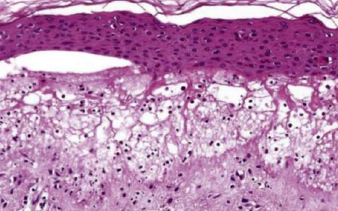

White Sponge Nevus

(Cannon disease)

體顯性 兩側的頰黏膜,出生時、孩童早期

• 口腔黏膜的正常角質化缺陷

• 對稱

• keratin 4 和 keratin 13 表現在上皮的棘狀上皮細胞層

• hyperparakeratosis, acanthosis

• spinous layer 清澈的細胞質

• 表層細胞核周圍嗜酸